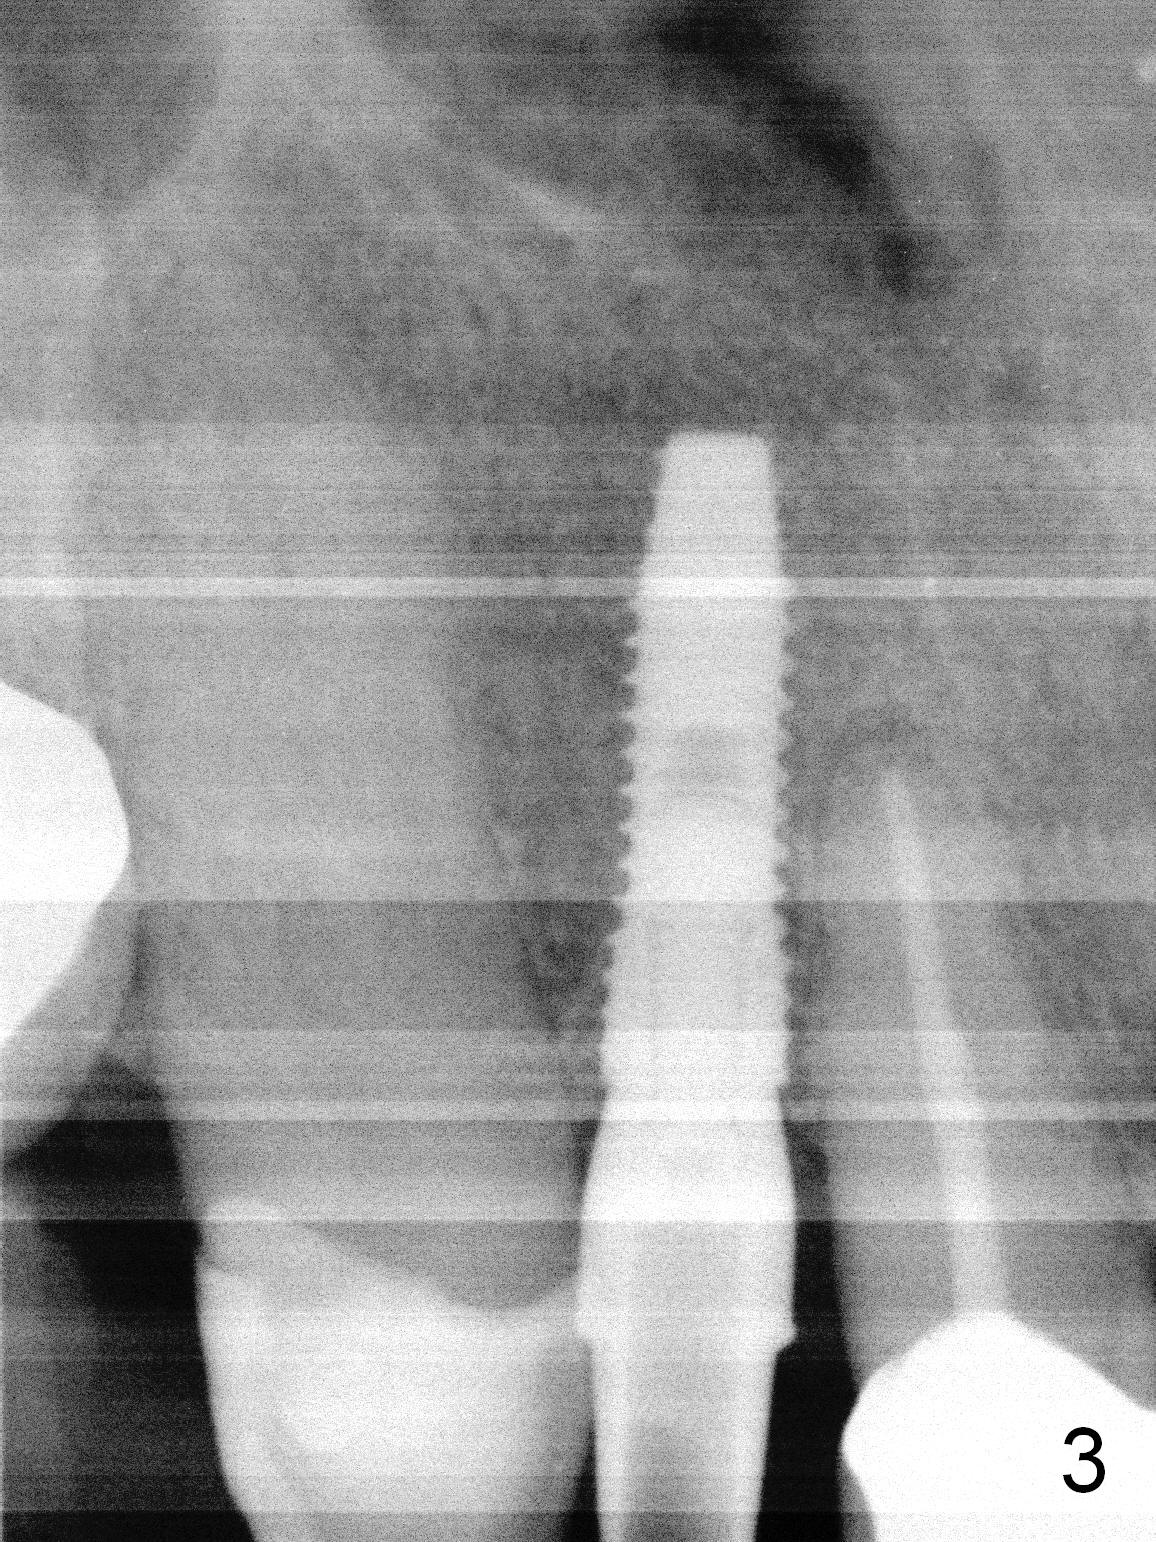

The residual root at #7 is fairly well exposed with buccal gingival recession (Fig.1). The implant placement is flapless (Fig.2-7). What is not shown is that the 3.8x13 mm implant is buccally subcrestally placed (Fig.3). After 1st round of bone graft buccal to the implant, a 4.5x5(5) mm abutment is immediately placed and prepared (Fig.4,5). An immediate provisional is placed after 2nd round of bone graft subgingivally buccally (Fig.6,7). Note the bulging gingiva (*), as compared to that in Fig.4,5. The long implant is chosen because of anterior deep bite (Fig.4) and lack of posterior support (Fig.7).

The gingiva adapts well to the provisional 1 week postop (Fig.8). The buccal gingiva remains recessive and the buccal plate is concave 5.5 months postop (Fig.9-11). It appears that the coronal portion of the buccal plate is resorbed 12 months postop (6 months post cementation, Fig.12 >). Socket shield or smaller diameter implant should have been done to avoid bone loss. Reanalysis of CBCT reveals that implantation apparently increases the bone width and that the buccal plate resorption is not so severe (Fig.13,14 (>: coronal end of the buccal plate)). Panoramic X-ray is taken 2 year 5 month post cementation.